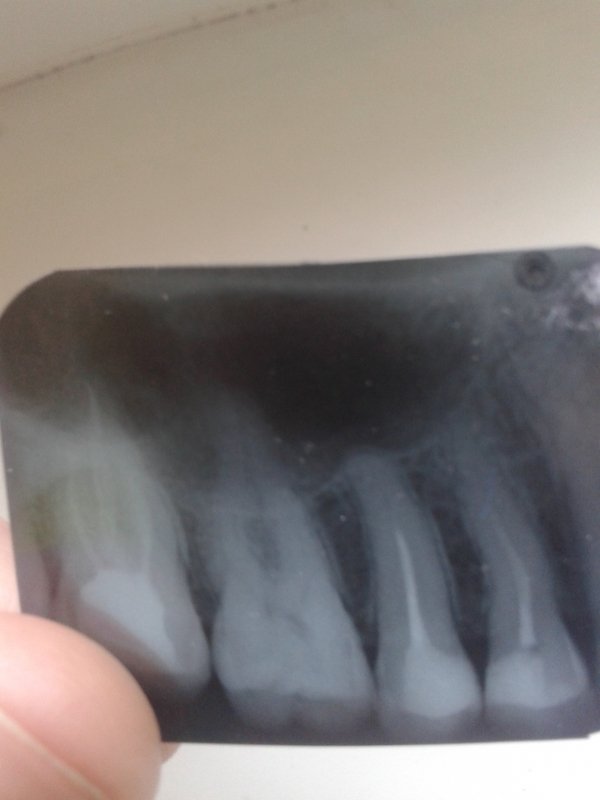

Здравствуйте. Беспокоит 7-ой зуб сверху слева (27). Зуб мертвый уже давно. Ноет, когда ему захочется. Иногда реагирует на температуру. Боль в обоих случаях терпимая, но неприятная. И сразу проходит. Мне его недавно залечили, прочищали каналы, положили туда хороший дорогой препарат, но это не помогло. Еще мне больно жевать что-то твердое. Боль ощущается то ли на этом зубе, то ли в промежутке между 7 и 6. В 1-ой клинике мне сказали, что есть гранулема и ее надо лечить с помощью микроскопа. Во 2-ой клинике мне сказали, что гранулемы нет. Прилагаю снимок.